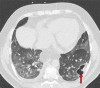

Chest CT has a potential role in the diagnosis, detection of complications, and prognostication of coronavirus disease 2019 (COVID-19). Implementation of appropriate precautionary safety measures, chest CT protocol optimization, and a standardized reporting system based on the pulmonary findings in this disease will enhance the clinical utility of chest CT. However, chest CT examinations may lead to both false-negative and false-positive results. Furthermore, the added value of chest CT in diagnostic decision making is dependent on several dynamic variables, most notably available resources (real-time reverse transcription-polymerase chain reaction [RT-PCR] tests, personal protective equipment, CT scanners, hospital and radiology personnel availability, and isolation room capacity) and the prevalence of both COVID-19 and other diseases with overlapping manifestations at chest CT. Chest CT is valuable to detect both alternative diagnoses and complications of COVID-19 (acute respiratory distress syndrome, pulmonary embolism, and heart failure), while its role for prognostication requires further investigation. The authors describe imaging and managing care of patients with COVID-19, with topics including (a) chest CT protocol, (b) chest CT findings of COVID-19 and its complications, (c) the diagnostic accuracy of chest CT and its role in diagnostic decision making and prognostication, and (d) reporting and communicating chest CT findings. The authors also review other specific topics, including the pathophysiology and clinical manifestations of COVID-19, the World Health Organization case definition, the value of performing RT-PCR tests, and the radiology department and personnel impact related to performing chest CT in COVID-19. ©RSNA, 2020.